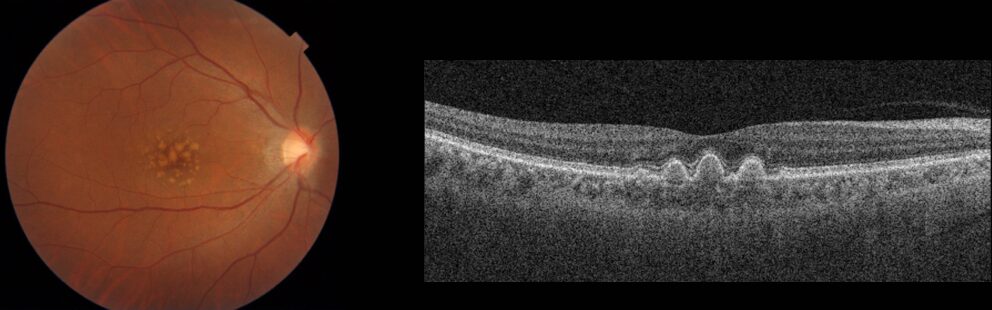

前駆病変ドルーゼン

加齢黄斑変性になる前段階として、黄斑部に老廃物がたまっている状態です。この場合も経過観察と生活習慣の改善が望ましいです。